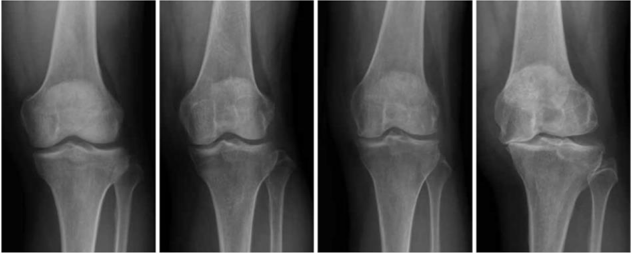

膝骨關節的X-ray分級(從左到右依次為1-4級)

膝骨關節炎是老年人膝蓋疼痛的主要原因。膝關節炎是一個有非常明顯階段性發展的疾病,根據疾病輕重可以分為初期、早期、中期和晚期四個階段。

現在對於膝關節炎的治療,都遵循“階梯治療”的理念,從初期到晚期,治療的難度和創傷都在遞增。大致的原則就是:優先“保膝”,實在不行再“換膝”。